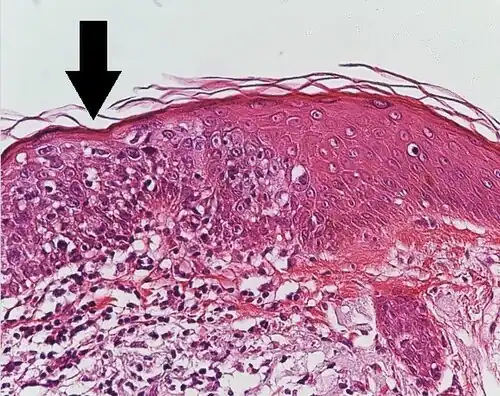

Histological characteristics

Histopathologically, the epidermis in cSCC in situ (Bowen's disease) will show hyperkeratosis and parakeratosis. There will also be marked acanthosis with elongation and thickening of the rete ridges. These changes will overly keratinocytic cells, which are often highly atypical and may have a more unusual appearance than invasive cSCC. The atypia spans the full thickness of the epidermis, with the keratinocytes demonstrating intense mitotic activity, pleomorphism, and greatly enlarged nuclei. They will also show a loss of maturity and polarity, giving the epidermis a disordered or "windblown" appearance.

Two types of multinucleated cells may be seen: the first will present as a multinucleated giant cell, and the second will appear as a dyskeratotic cell engulfed in the cytoplasm of a keratinocyte. Occasionally, cells of the upper epidermis will undergo vacuolization, demonstrating an abundant and strongly eosinophilic cytoplasm. There may be a mild to moderate lymphohistiocytic infiltrate detected in the upper dermis.[12]

Histopathology of squamous-cell carcinoma in situ (black arrow), compared to normal skin, showing marked atypia.

Histopathology of squamous-cell carcinoma in situ (black arrow), compared to normal skin, showing marked atypia. -

![Squamous-cell carcinoma in situ, showing prominent dyskeratosis and aberrant mitoses at all levels of the epidermis, along with marked parakeratosis.[12]](./Micrograph_of_squamous_cell_carcinoma_in_situ_-_100x.jpg) Squamous-cell carcinoma in situ, showing prominent dyskeratosis and aberrant mitoses at all levels of the epidermis, along with marked parakeratosis.[12]

Squamous-cell carcinoma in situ, showing prominent dyskeratosis and aberrant mitoses at all levels of the epidermis, along with marked parakeratosis.[12]